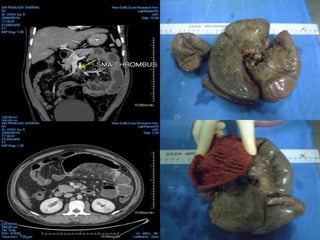

SMV THROMBOSIS

SMA THROMBOSIS SMV THROMBOSIS

ARTERIAL OCLUSIVE ISCHEMIAVENOUS OCLUSIVE ISCHEMIA SMA THROMBOSIS SMV THROMBOSIS NO /SUBTLE BOWEL ENHANCEMENT HYPO/HYPERDENSE BOWEL WALL THINNED BOWEL WALL (PAPER THIN BOWEL ) SIGNIFICANT BOWEL WALL THICKENING NO MUCOSAL ENHANCEMENT MUCOSAL ENHANCEMENT BOWEL LOOP DILATATION ONLY AFTER INFARCTION DILATED BOWEL LOOPS WITHOUT INFARCTION LATE STAGES –MESENTERIC FAT STRANDING,EDEMA/HEMORRHAGES MARKED FAT STRANDING AND HEMORRHAGE

63-year-old woman statuspost aortic valve replacement who presents with a one week history of abdominal pain becoming quite severe over the last 24 hours.